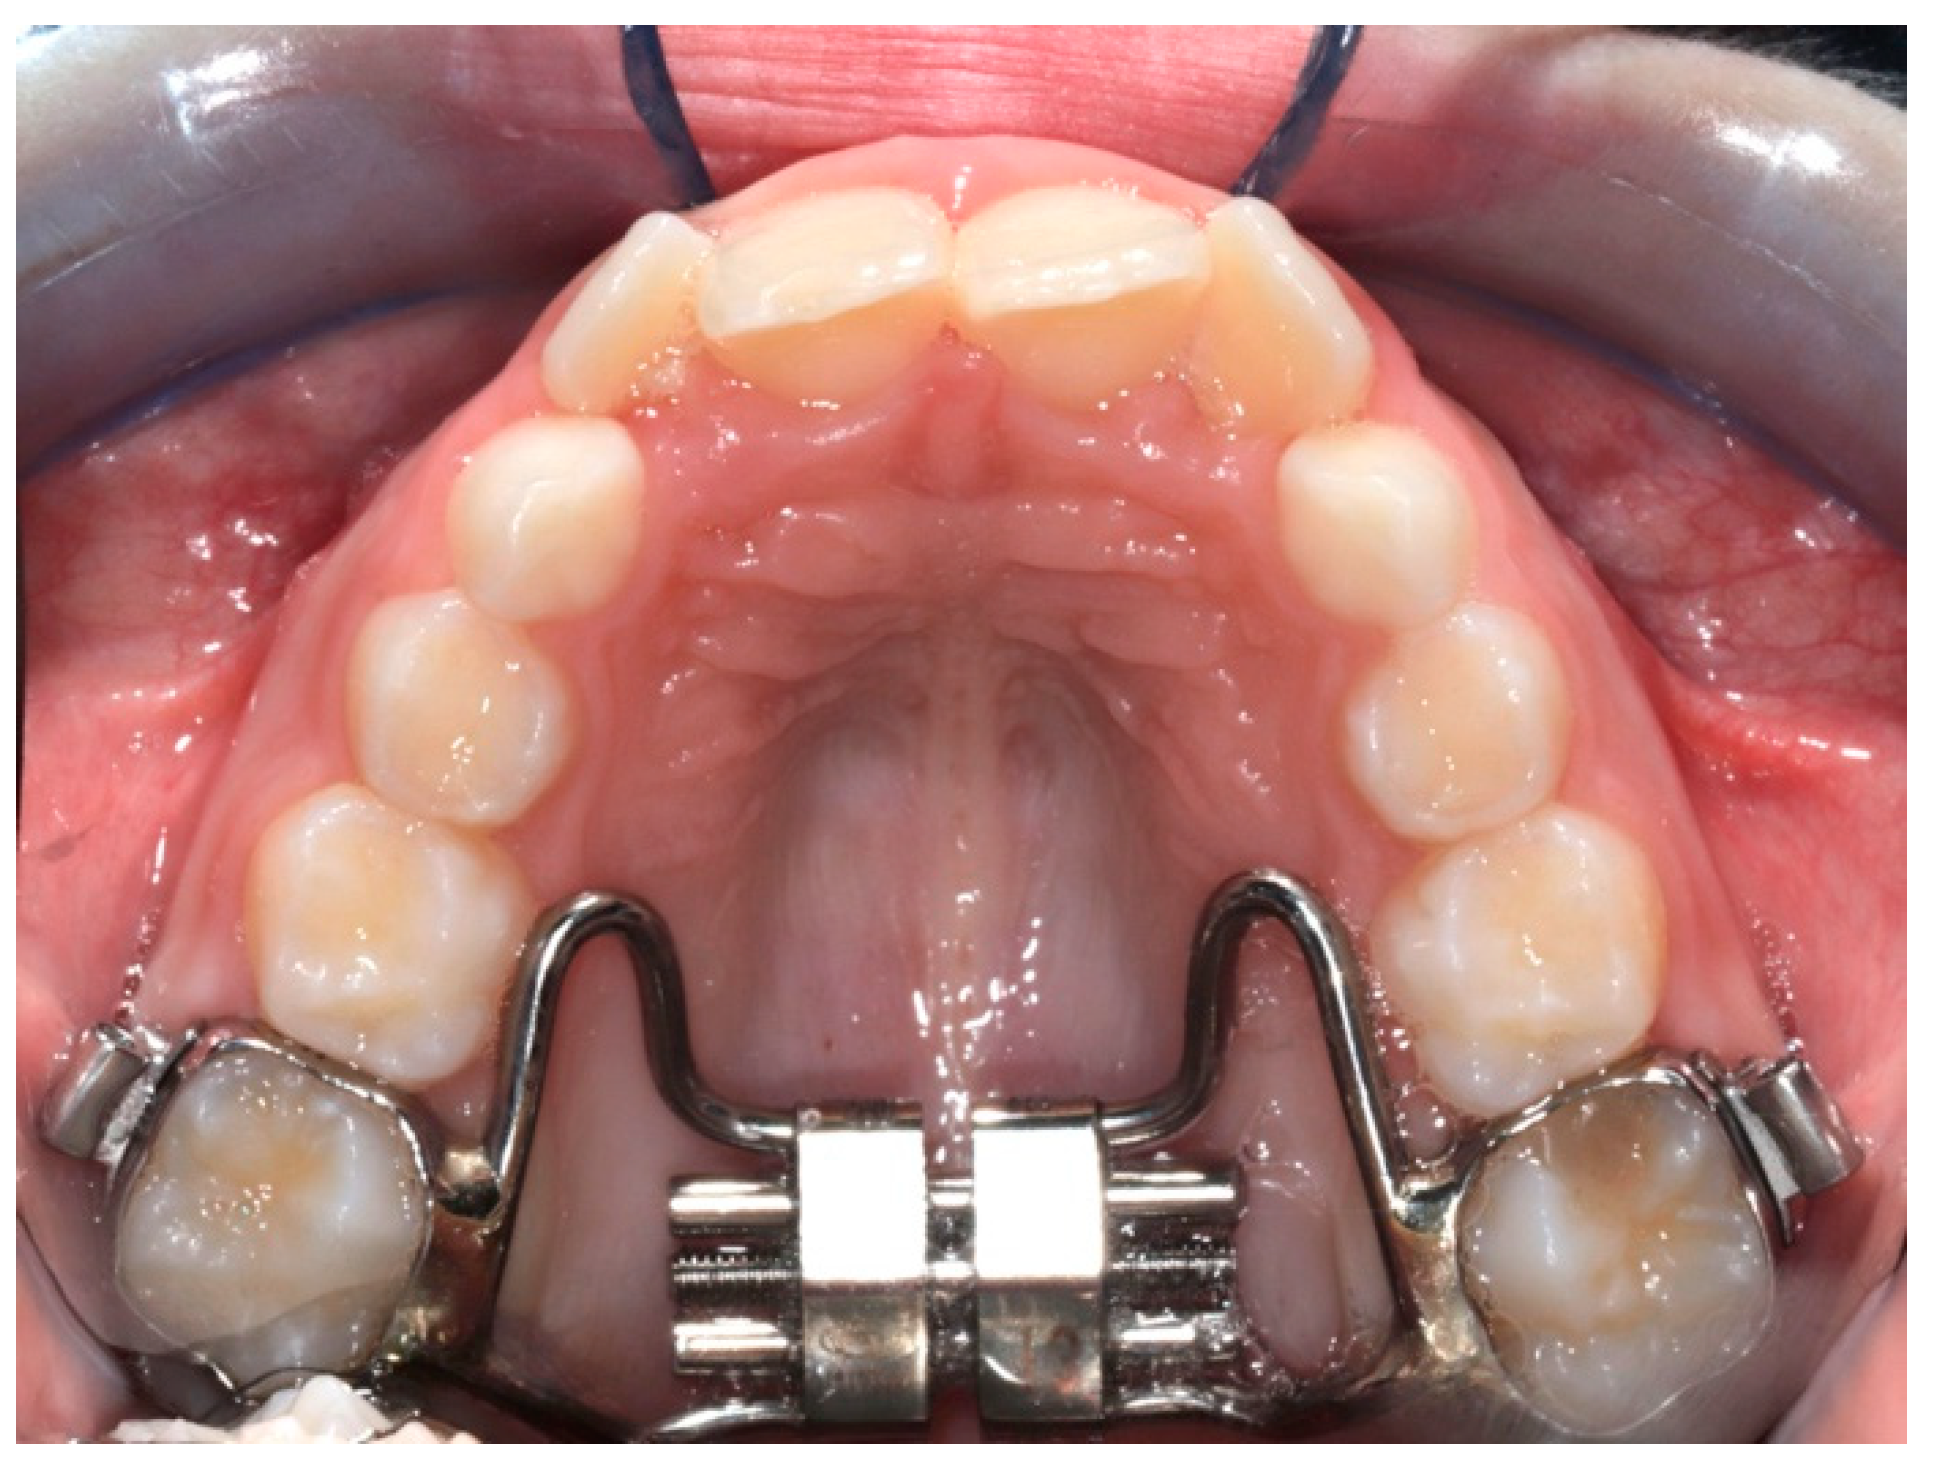

The digital dental casts of 32 children consecutively treated with either RME (Figure 1) (RG: n = 17, 8 males, 9 females; mean age 8.1 ± 0.8 years) or the Invisalign® First system (Figure 2) (FG: n = 15, 7 males, 8 females; mean age 8.4 ± 1.1 years) were collected. The study subjects were retrieved from the records of patients treated at the Department of Orthodontics at the University of Rome “Tor Vergata”.

The RME group (RG) subjects were treated with a butterfly palatal expander (expansion screw with telescopic guides, A2620—Leone SpA, Sesto Fiorentino, Firenze, Italy) [30]. This appliance has a butterfly-shaped stainless-steel framework banded on the first maxillary molars that extend forward to the palatal surfaces of the maxillary deciduous molars, and the activation of the screw commenced immediately after the appliance was cemented in place.

In the RG, the RME expansion screw was activated by the patients’ parents at a 1/4 turn per day (one activation, 0.25 mm per turn) until overcorrection was achieved (i.e., the palatal cusps of the maxillary posterior teeth approximated the buccal cusps of the mandibular posterior teeth). The RME was kept in place on the teeth as a passive retainer stabilizing the expansion reached during the screw activation and was removed 8 months after the application. During the active phase of treatment, the patients were checked every 2 weeks to monitor the activation of the screw. In addition, in this group of patients, the average treatment time was 8 months, and intra-oral scans were taken 3 months after the end of active therapy to create digital dental casts.

Figure 2. Conventional RME.